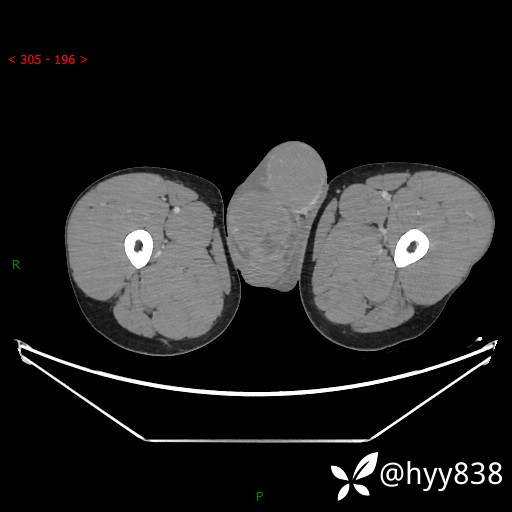

静脉期